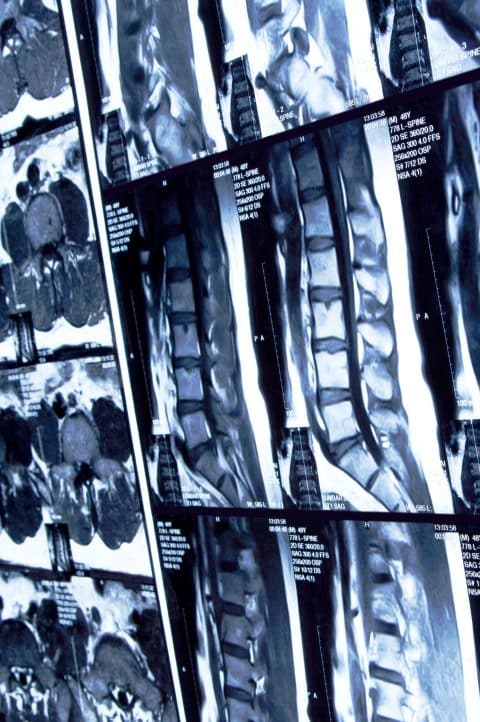

How Are Spinal Cord Injuries Diagnosed?

Once there, doctors and other health care providers perform a physical exam to determine the exact location of the injury. Further tests may include: (24)

- A CT (CAT) scan.

- An MRI to give health care providers “a picture” of the injury.

- X-rays, or a myelogram (injecting dye before X-raying the spine).

- Electromyography (or EMG, which checks muscles and the nerves that control them).